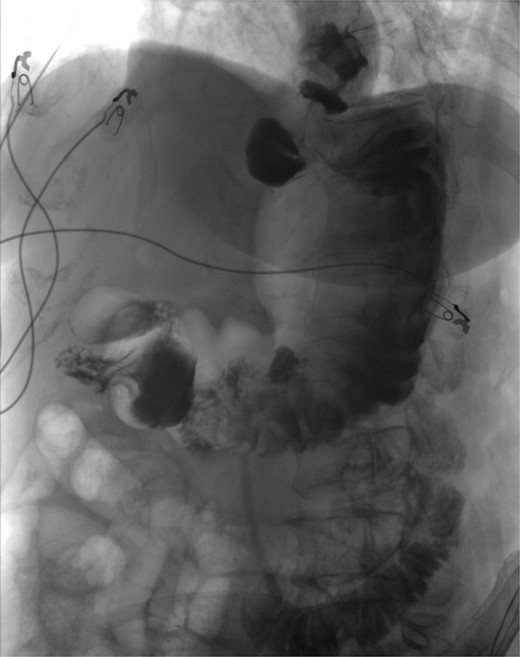

Operative findings revealed gastric body herniation under the antrum and pylorus, causing 180° twisting of the stomach and obstruction of the antrum, consistent with mesenteroaxial volvulus. The gastrohepatic ligament was absent, and the greater curvature was nearly fully mobilized from the prior Nissen. The volvulus was laparoscopically reduced to restore normal anatomy, and a gastrostomy tube was placed to pexy the stomach to the abdominal wall to prevent recurrence. Finally, as an additional precaution, 10 units of Botox were injected into the pylorus to treat her possible gastroparesis diagnosed prior to her acute presentation. Postoperative course was uneventful. An upper GI study completed on postoperative Day 1 was negative for contrast leak (see Fig. 4). She was discharged home on postoperative Day 5. At her follow-up visit, she reported resolution of all symptoms.